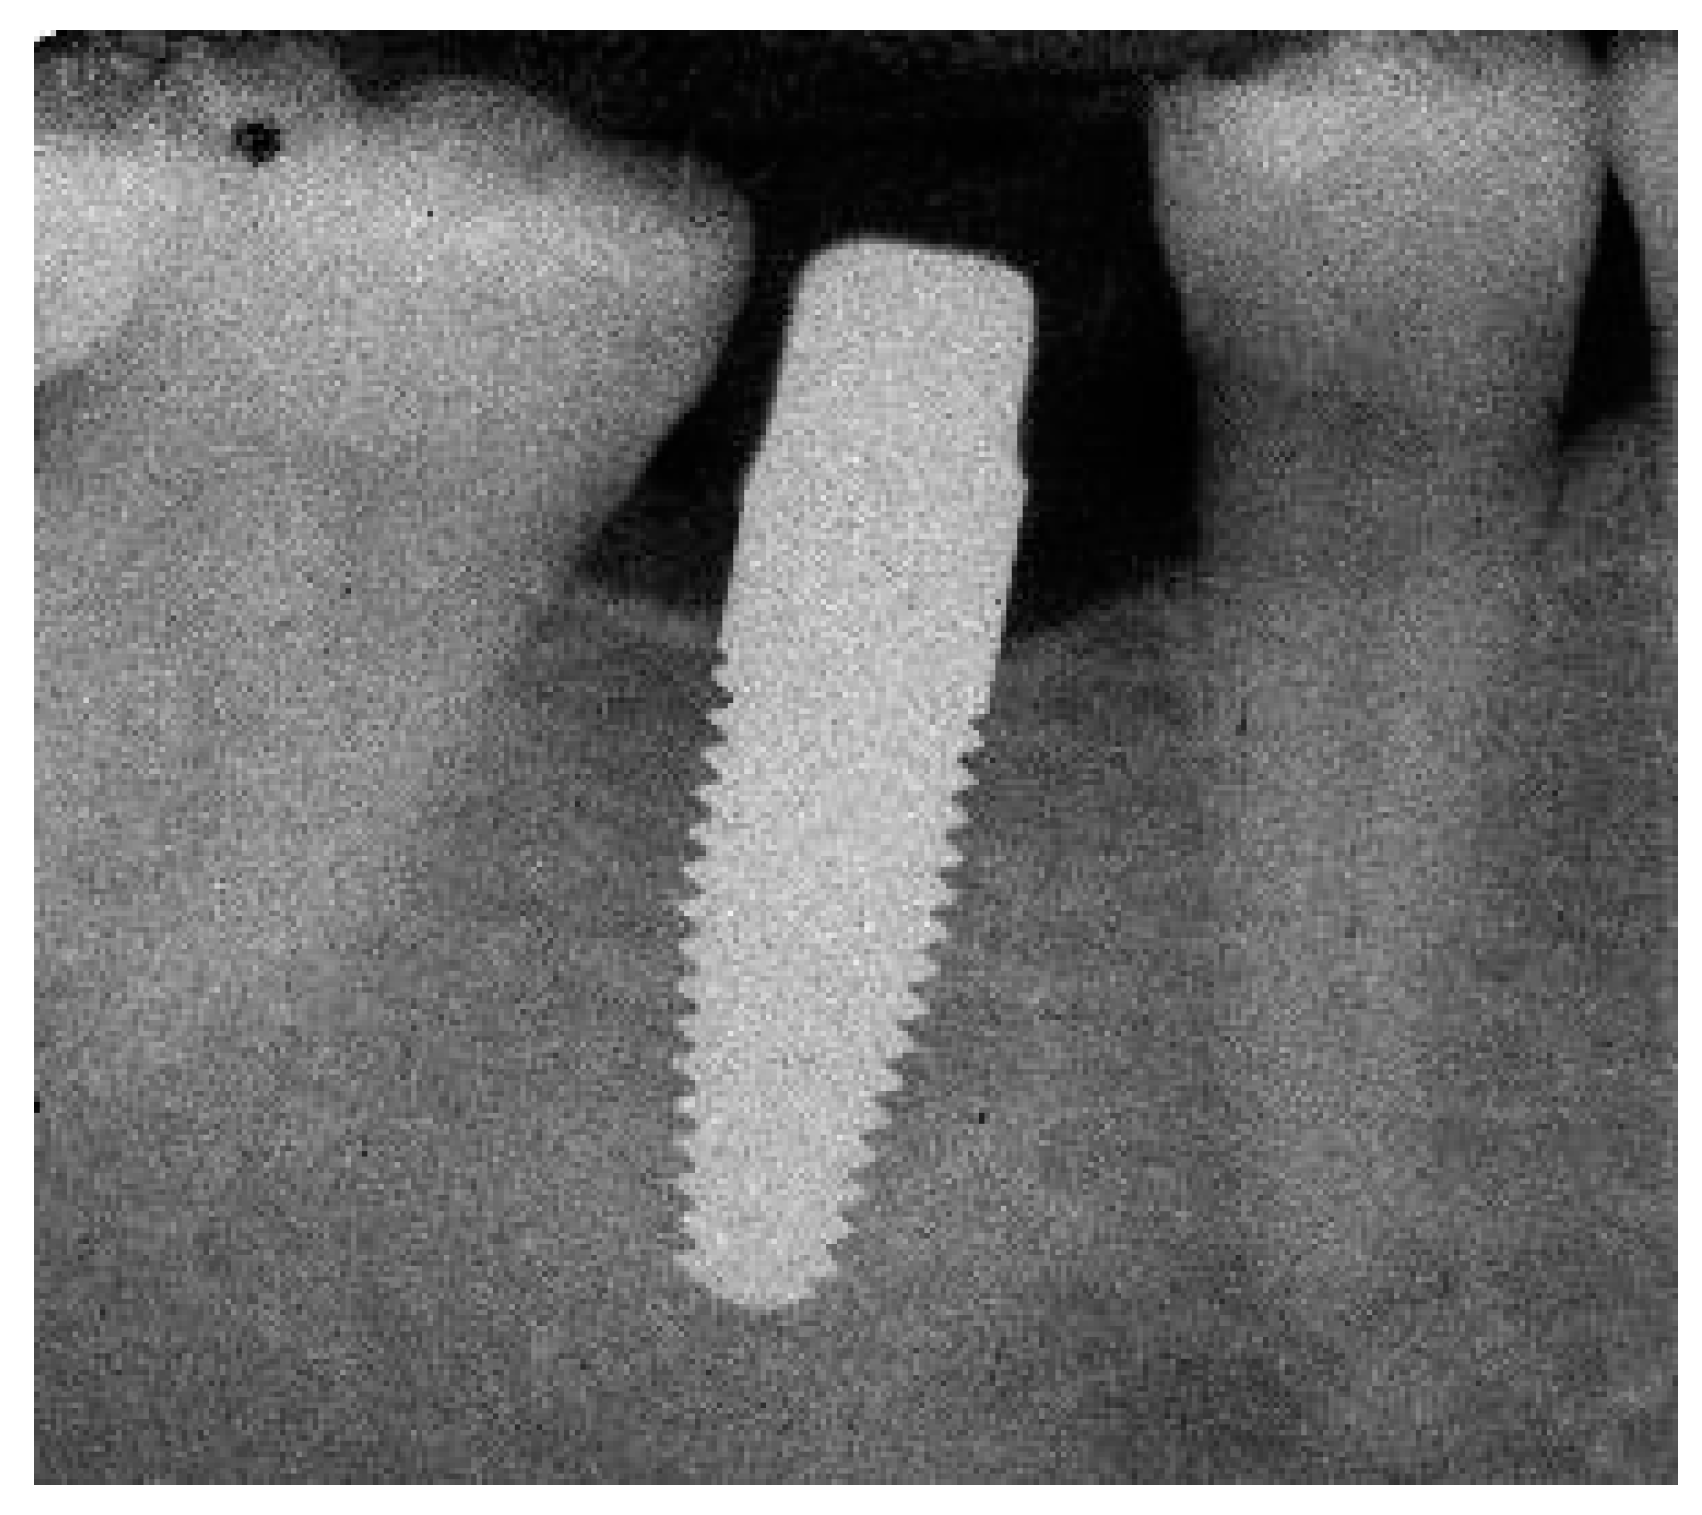

Figure A3.

Figure A6.

Figure A9.

Figure A12.